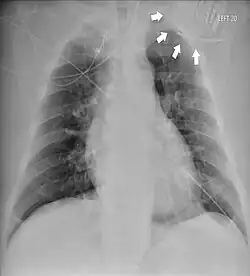

| Chest radiograph showing twiddler's syndrome. The leads of the automated external defibrillator are wrapped around the device and can't be seen in the ventricle. | |

Given its speed and ability to provide a clear image of the lead coiling and device rotation, the chest X-ray is the most straightforward and important diagnostic tool for Twiddler's syndrome.[3]